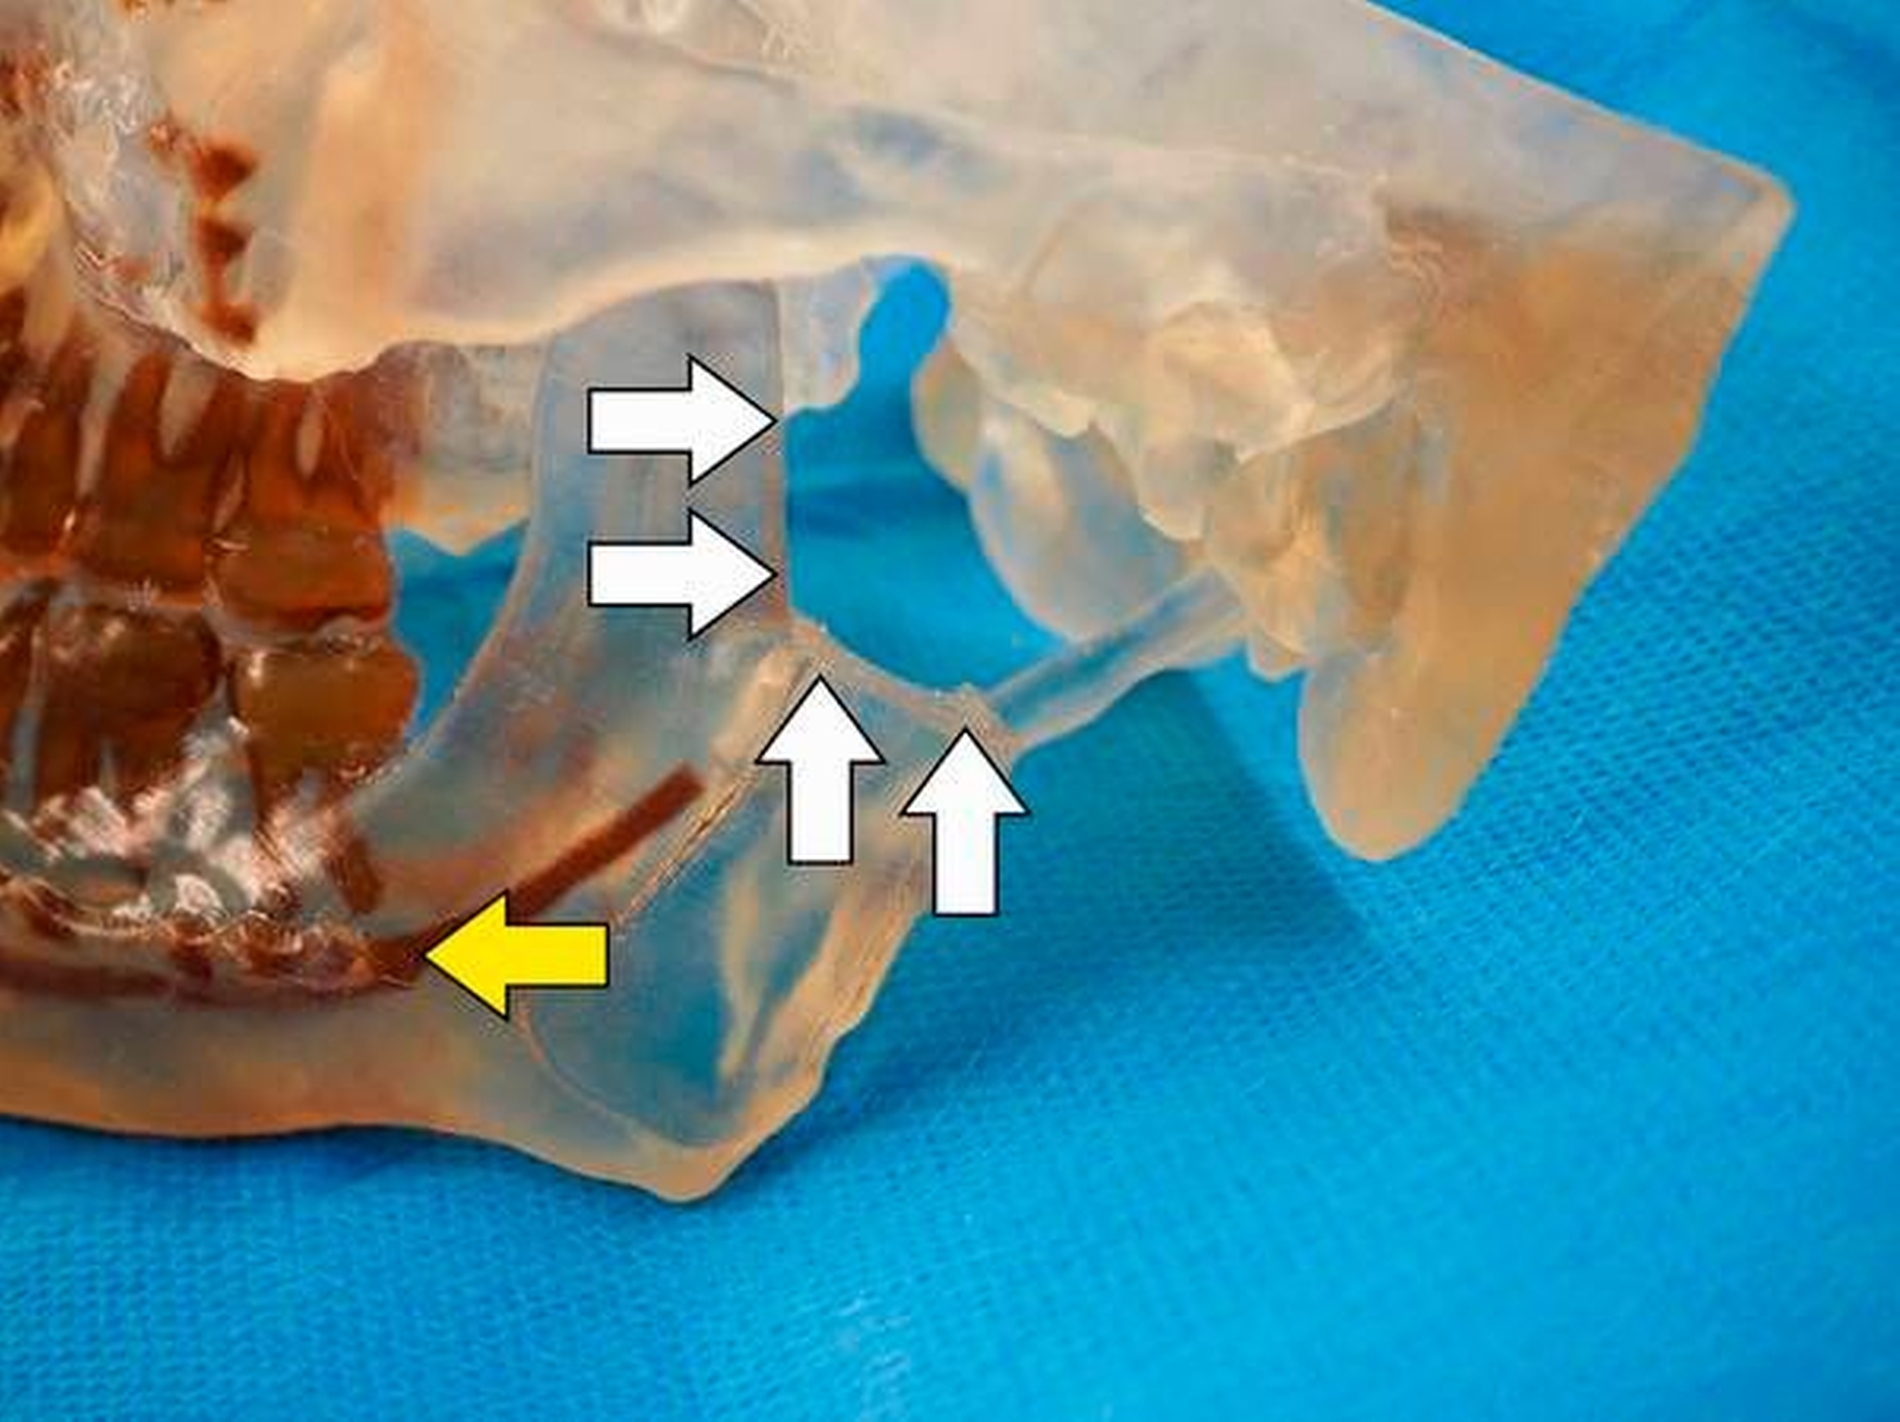

Vorgeschlagen wurde dem Patienten der totale Gelenkersatz beidseits – mit auf Basis der CT-Daten individuell erstellten Fossa-Komponenten aus einem speziellen Kunststoff (Ultra High Molecular Weight Polyethylene) und individuellen Gelenkkopfprothesen aus einer titanbeschichteten Chrom-Kobalt-Legierung (Biomet Microfixation Inc., Vertrieb Zimmer Biomet Deutschland GmbH). Der Patient und seine Angehörigen wurden in intensiven Gesprächen über die Vorteile und Risiken des Eingriffs aufgeklärt.

Nach Akzeptanz des Behandlungsplans wurden die TEPs (Totalendoprothesen) beidseits über jeweils einen präaurikulären und einen retromandibulären Zugang implantiert. Diese Prothesen wurden mit Schrauben – mit exakt am CT-Datensatz definierten Schraubenlängen – fixiert. Bei der Planung der Schraubenpositionierung wurde der Verlauf des N. alveolaris inferior berücksichtigt und der Nerv geschont.

Vor der definitiven Fixierung der Prothesen wurden Dummys als Test eingesetzt, um eine optimale Positionierung der passgenauen finalen Prothesen zu erreichen (Abbildung 2 bis 9). Abbildung 10a und 10b zeigen die postoperative Röntgenkontrolle.